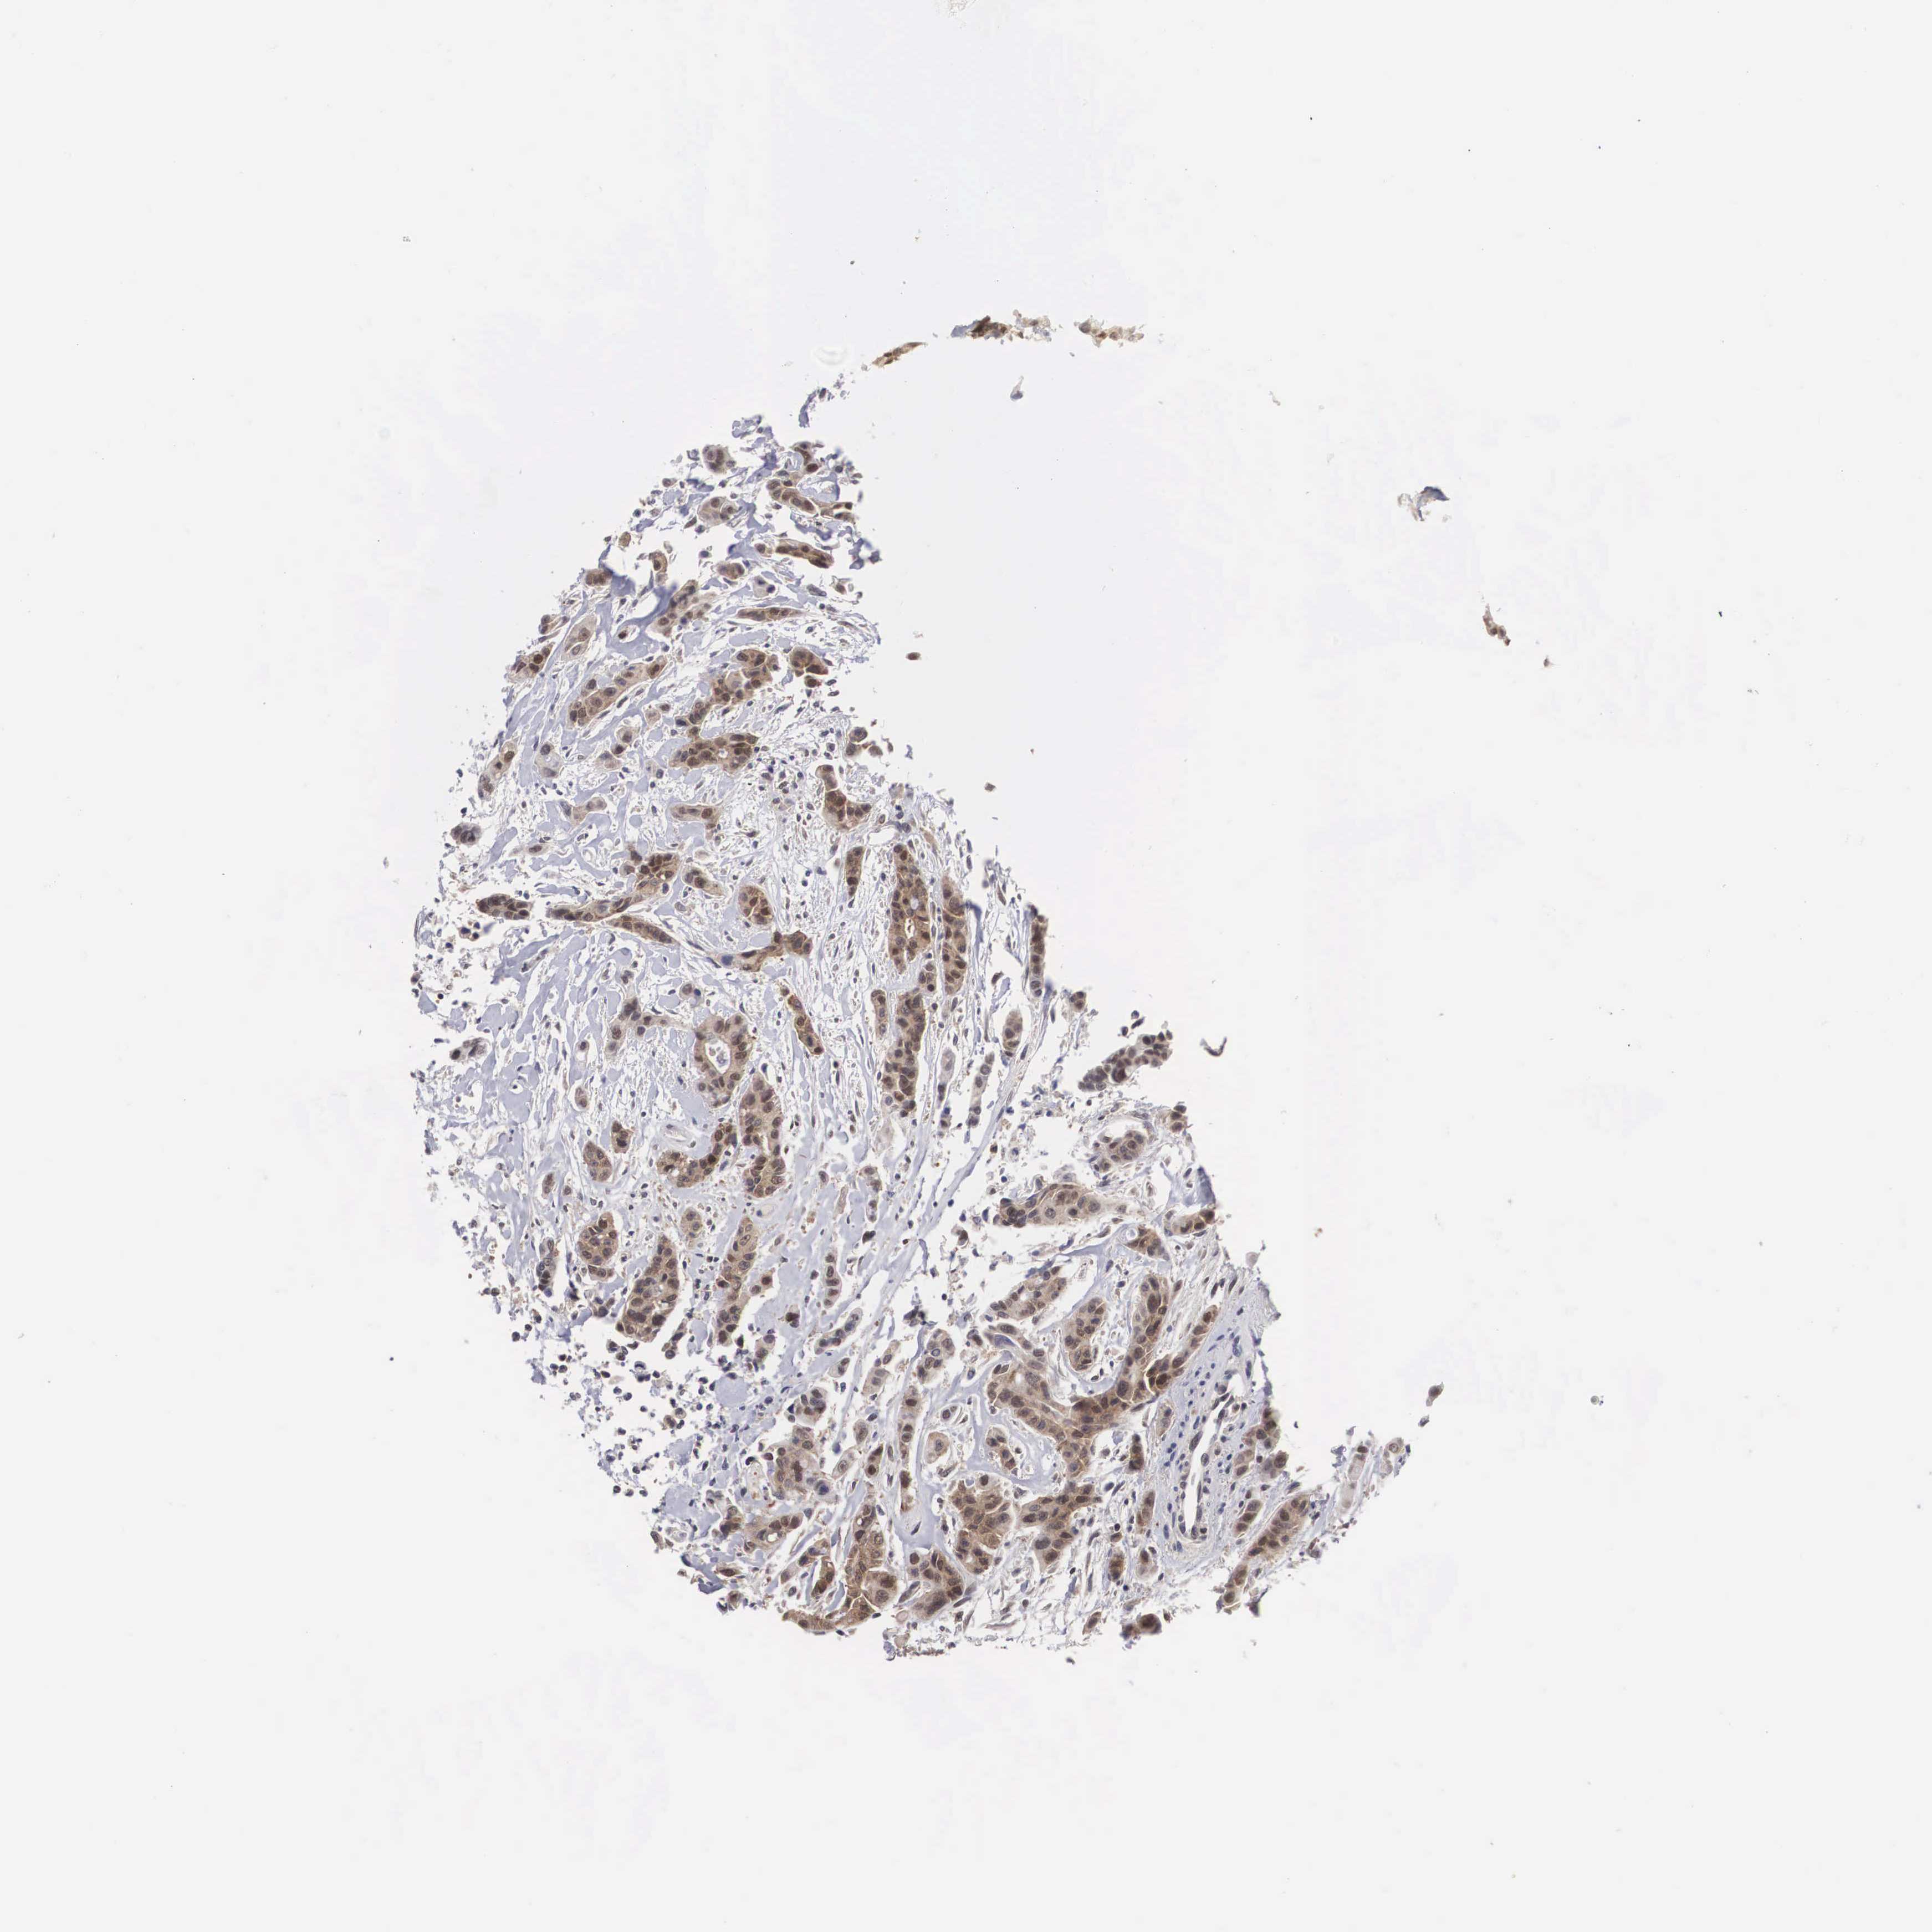

CANCER COLORECTAL CANCER Show tissue menu

ANTIBODIES

AND

VALIDATION